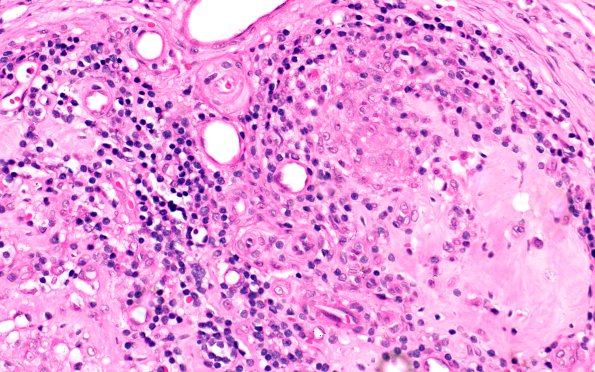

8A4 Leprosy, Tuberculoid (Case 8) 40X 1

Classic tuberculoid leprosy. (H&E)